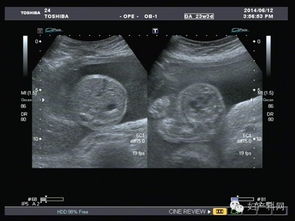

超聲波檢查,通過超聲波檢查出胎寶寶的體重、位置、大小。胎盤位置、羊水?dāng)?shù)量、呼吸運(yùn)動等情況,以便判斷是進(jìn)行自然分娩還是剖腹產(chǎn)

特別是對于月經(jīng)不準(zhǔn)或者記不清楚最后一次月經(jīng)的孕媽媽來說,在懷孕早期可以利用超聲波檢查預(yù)見預(yù)產(chǎn)期。還可以檢查胎兒是否缺氧,或者孕婦是否是宮外孕。但是,超聲波最主要的還是堅(jiān)持寶寶在腹中的生長情況。

現(xiàn)代社會,雖然科技在不斷發(fā)展,但是環(huán)境也在受到更嚴(yán)重的污染,這就導(dǎo)致了許多畸形胎兒的生長,而超聲波檢查就能告訴你胎兒生長是不是正常,是否有什么缺陷,有特別的情況的話,醫(yī)生通過超聲波檢查可以告訴你,比如,有些遺傳病可以在寶寶出生之前檢查出來,比如營養(yǎng)性肌肉發(fā)育不良,如果是男孩的話很容易造成遺傳,這樣的話醫(yī)生會通過檢查結(jié)果告訴你最好不要孩子。

一般來說,在第18周-20周進(jìn)行第一次超聲波檢查。它能大致診斷出胎兒是否畸形,觀察胎兒的活動狀態(tài)。

在懷孕第34周第二次超聲波檢查的目的是監(jiān)測羊水量、胎盤位置、胎盤成熟度及胎兒有無畸形,了解胎兒發(fā)育與孕周是否相符。 最后是在第37周以后,超聲檢查主要目的是確定生產(chǎn)方式,為了監(jiān)測羊水量、胎盤成熟度,必要時需要每周一次B超。